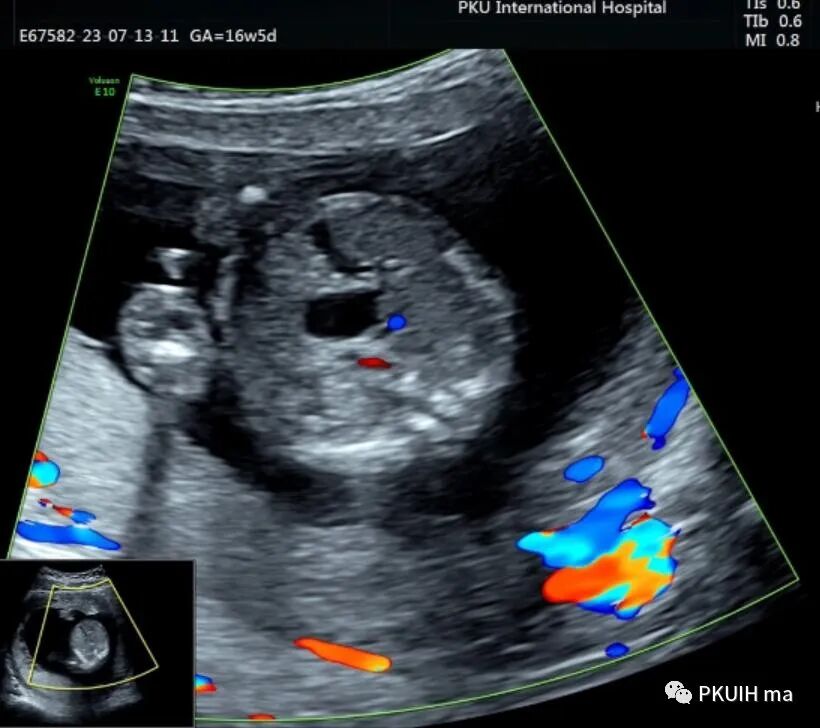

胎儿中腹部见一囊性包块,大小约1.2x1.0x0.8cm,边界清,形态规则,内透声好。囊肿位于脊柱前方、胆囊后方、门静脉窦旁,与后肾接近

观察囊肿与肾、胃泡、膀胱均无相关。

仔细观察囊肿壁好像不完整,周边见微小管道回声与囊肿相通

CDFI:囊肿内未见明显血流信号。

由于囊肿位于胆囊后方、肝下方、门静脉窦旁,随考虑为胆总管囊肿

本病可于中孕及晚孕期被发现,其超声特征为肝门区囊性包块,形状呈圆形或椭圆形,位于门静脉右前方,可对门脉造成压迫。如果显示囊性包块与胆囊相通,则有助于诊断,彩超一般内部无血流信号。